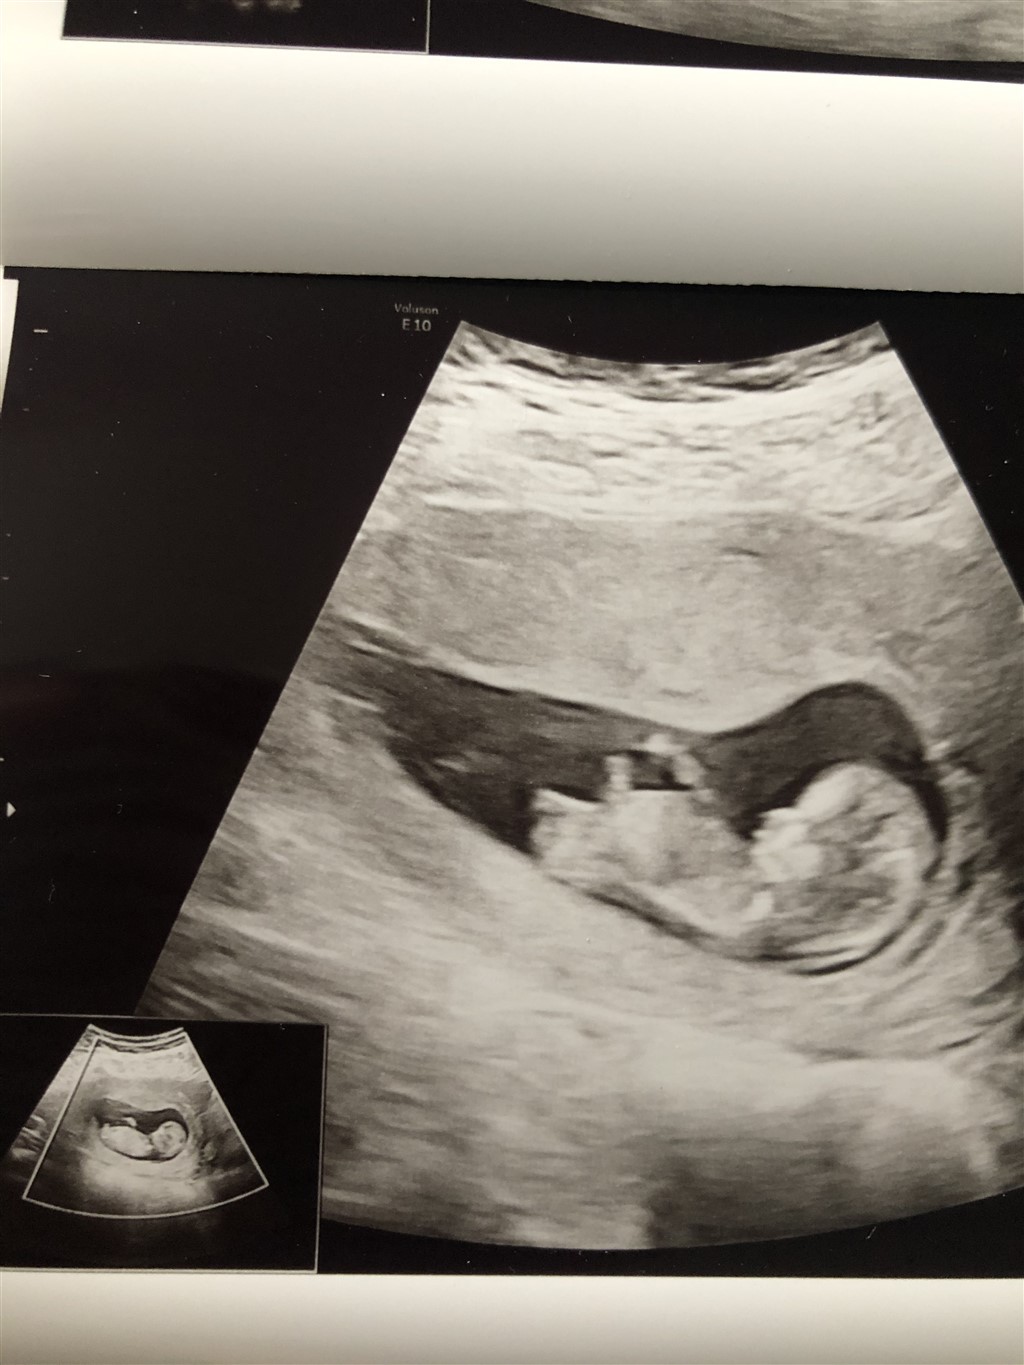

Jeg fik Jordmoderen til at tage det bedst mulige billede i forhold til at se det. Jeg er 12+0 i morgen.

Hvad gætter i på og hvorfor?